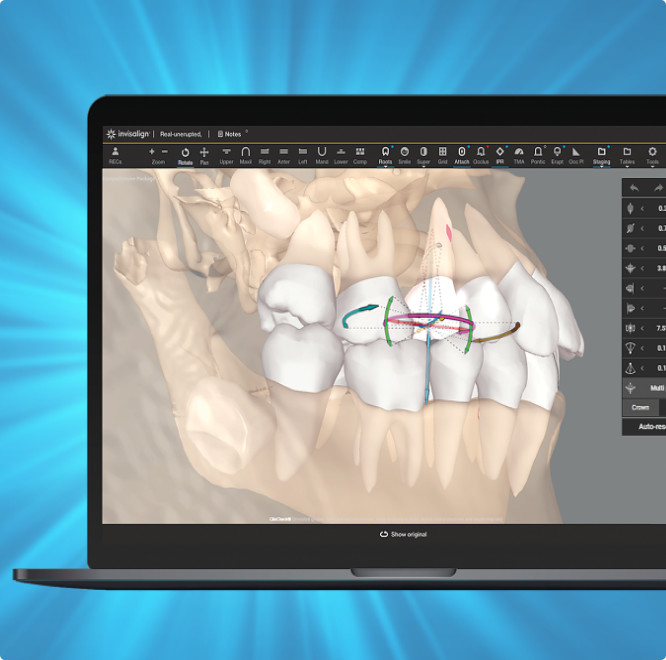

Start your treatment planning process in ClinCheck Pro leveraging the now enabled “Roots” button in the tool bar.

Start your treatment planning process in ClinCheck Pro leveraging the now enabled “Roots” button in the tool bar.

Three new views in one integrated platform to enhance treatment planning.

Roots only

Roots with semitransparent bone

Roots and bone